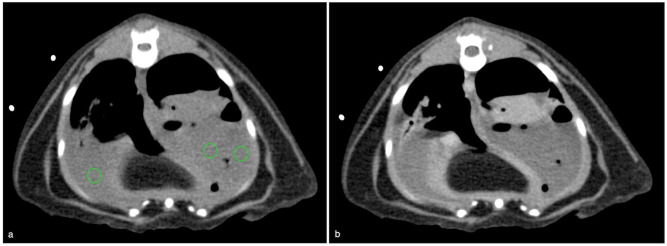

ObjectivesThe purpose of this retrospective, descriptive study was to assess CT findings and short-term outcome of cats with pyothorax presented to a referral hospital.MethodsThoracic CT studies of 41 cats with pyothorax comprising pre-contrast lung and soft tissue reconstructions and post-contrast soft tissue reconstructions were blindly reviewed by two European College of Veterinary Diagnostic Imaging (ECVDI) board-certified radiologists and a third-year ECVDI resident, referencing a predetermined list of imaging features. Clinical outcomes, including treatment options, survival to discharge and length of hospitalisation, were recorded.ResultsAll cats (100%) had pleural effusion. Common imaging findings included intrathoracic lymphadenomegaly (85%), pleural thickening (85%), presence of pannus (81%) and evidence of pneumonia (49%). Pulmonary abscessation was suspected in 22% of cats and foreign bodies in 12%. Of the 41 cats, 20 were managed medically, 20 underwent surgery and one had unsuccessful medical treatment followed by surgical intervention. The median duration of hospitalisation was 7 days, and 36 cats survived to discharge.Conclusions and relevanceThis study demonstrates that cats with pyothorax commonly have marked changes on CT that involve multiple thoracic compartments. Our study population highlights that feline pyothorax can have a good short-term outcome when managed either medically or surgically.

Abstract Image